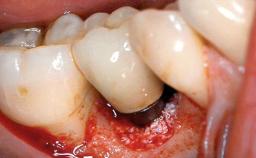

Retreatment of a Patient with Multiple Biological and Technical Complications and Failures

A 66-year-old patient presented because of retention loss of the tooth-supported FDP in the right maxilla (x-13-x-11). The mandibular full-arch implant-supported reconstruction (x-i34-i33-x-x-x-x-i43-i44-x) had suffered extreme wear. His medical history revealed high blood pressure, controlled with anti-hypertensive medication. The patient was a light smoker (2 to 3 cigarettes per day). The existing reconstructions had been performed alio loco about five years previously. That treatment had taken an extensive amount of time, and as early as during the fabrication of the reconstructions, multiple complications had occurred with the provisionals.